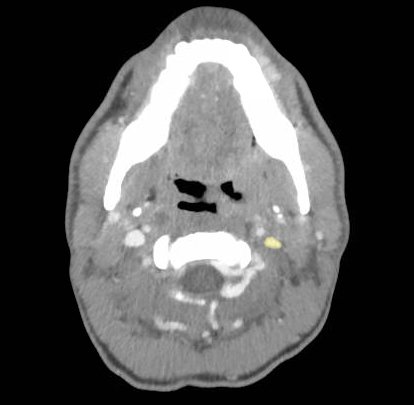

The photograph demonstrates an area of ulcerative tissue at the left palatine tonsil without surrounding erythema or purulent drainage. The computed tomography (CT) scan shows a large ulceration of the left soft palate and palatine tonsil (red arrow). There is no evidence of skull base osteomyelitis. There is suppurative lymphadenopathy with partial left jugular vein compression due to mass effect (yellow highlight). There is mild nasopharyngeal airway narrowing with architectural distortion (blue arrow), but no other evidence of airway obstruction.